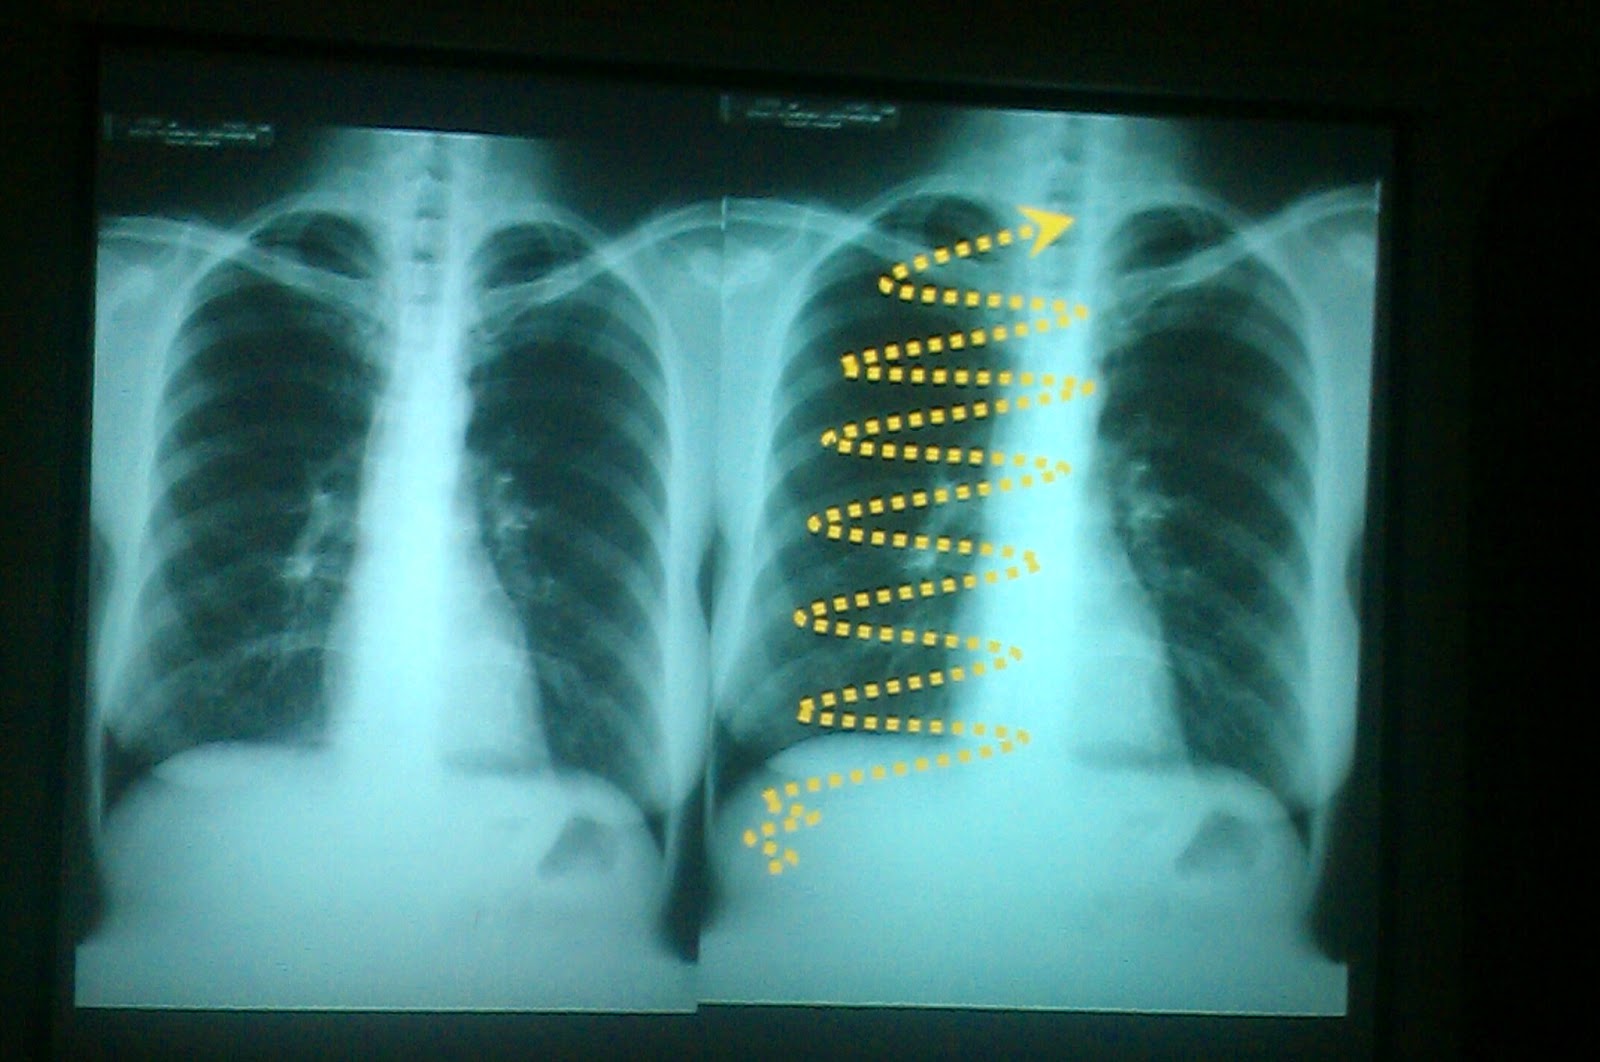

From www.youtube.com

Chest X ray Lecture 01 Part 03 YouTube Chest X Ray Lecture Understand the key concepts of reading a chest radiograph with this. In fact every radiologst should be an. — a description of a systematic method for examining a chest x. a free medical lecture on chest x ray (cxr) interpretation. Chest X Ray Lecture.